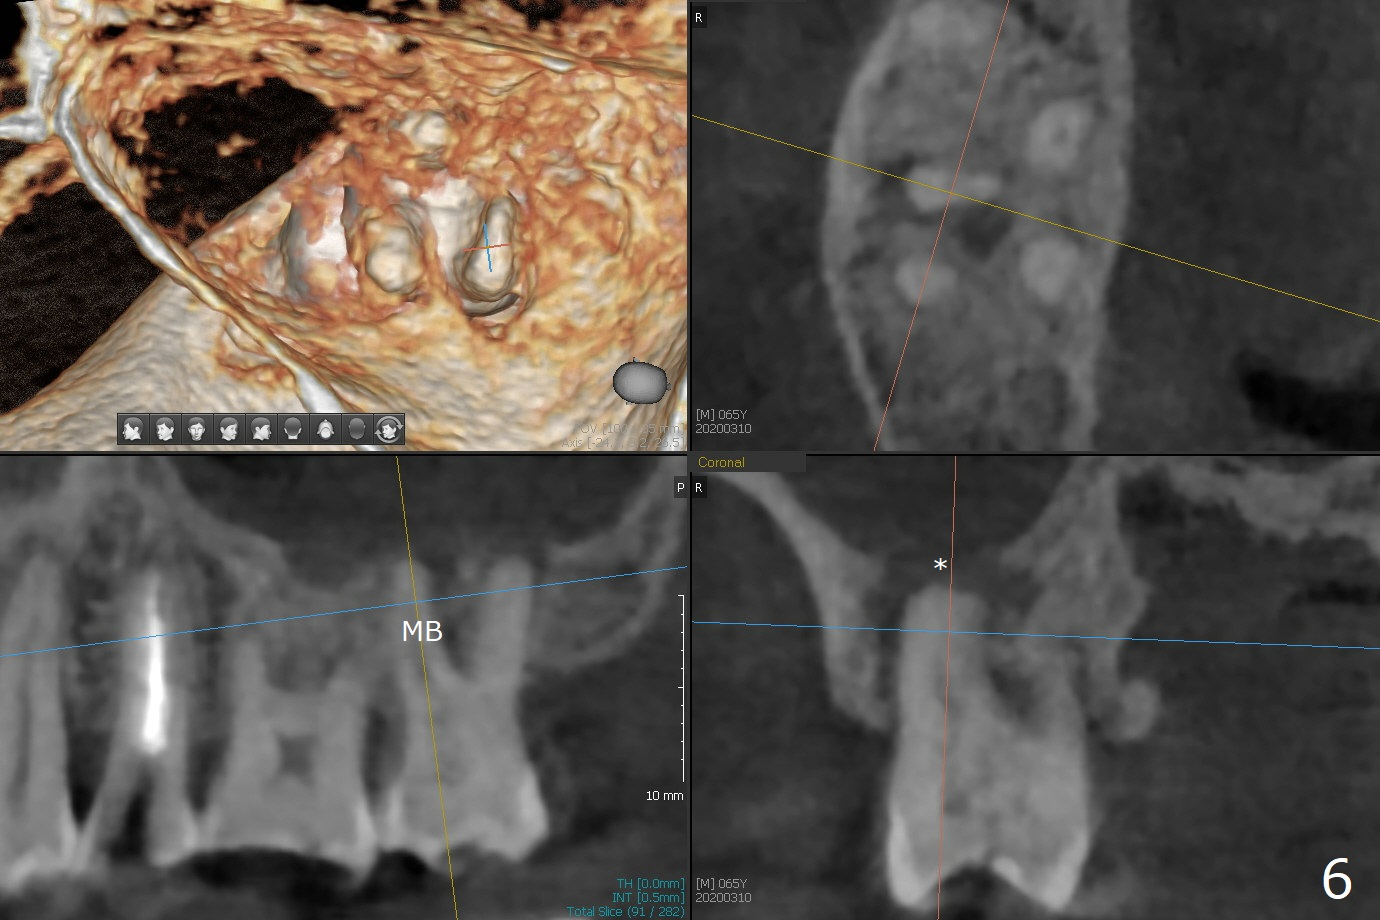

After implant placement at #13 six months post bone graft (Fig.1), reexami-nation shows that the tooth #2 cracks (Fig.2-4). The bony defect area is easier to identify with CT (between MB and P roots of #2) than without CT (M) for #13. There is no bone height reduction after extraction of #15 (Fig.5). Due to new coronal virus outbreak, the patient wants extraction first. The sinus floor perforates (*) apical to MB (Fig.6) and DB (Fig.7) roots. After debridement, sinus lift will be conducted using allograft hydrated with GEM21S liquid portion. The same mix will be used for socket preservation. With high concentration of growth factor, it is hoped that bone density in the sockets will increase quick and high enough for future implant, as compared to #13 of the same patient.